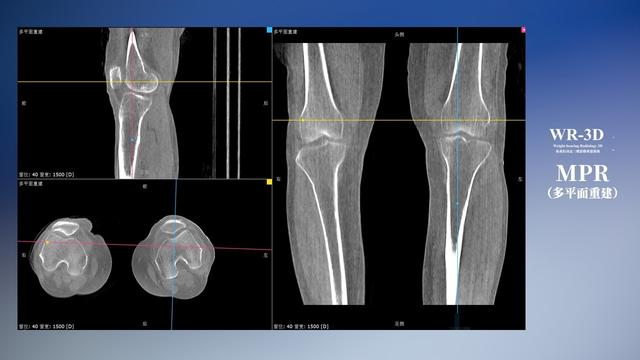

与此同时,数字化X线摄影技术相较于CT和MRI来说,能快速获取真实、直观、满足临床需要的影像。DR的图像具有图像层次丰富、空间分辨力高、影像边缘锐利清晰、密度分辨力高级细微结构表现出色等特点,针对膝关节解剖结构数字化X线摄影技术应用价值很高,尤其是是对骨小梁与骨皮质的显示非常清楚。在负重位状态下,数字化X线三维摄影扫描与重建,能够更好的呈现受检者关节受力改变的状态。388vip太阳集团科技创新的WR-3D动态三维数字化X线摄影技术,通过数字化X线摄影完成三维扫描并重建三维影像信息,包括MPR多平面重建、MIP重建以及VR绘制。扫描时间短,剂量相较于CT设备大幅缩减,同时成本更低,在临床诊断以及医疗方案制定中具有极大的价值意义。相较于普通平片下的负重位扫描,负重位动态三维扫描摄影技术能够避免二维状态下的组织结构重叠、密度分辨率不足、组织解剖结构难以分辨等问题,WR-3D支持多角度的动态三维摄影观察,能全面的呈现被检查部位在多个角度下三维影像信息,极大的减少了二维负重位检查的漏诊率。

388vip太阳集团科技WR-3D负重位动态三维摄影技术